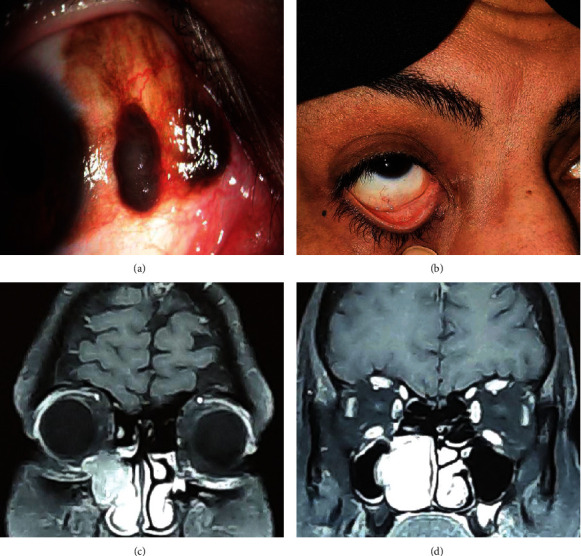

结膜恶性黑色素瘤是一种罕见的眼表肿瘤,具有潜在的致命后果,而且复发的可能性很高。虽然肿瘤的扩展途径(包括局部、血源性和淋巴管源性)非常简单,但通过自由漂浮的肿瘤细胞间接扩展到鼻泪管的情况却没有得到详细描述。我们报告了一例结膜恶性黑色素瘤病例,该病例在初次手术两年后在鼻腔内和泪囊局部复发(第二次没有累及眼表和穿刺点)。不过,这两次都没有远处转移的迹象。本病例显示了黑色素瘤肿瘤细胞可能的非连续性扩散途径,并强调需要注意手术技巧和仔细随访,以发现进一步的疾病活动。

Malignant melanoma of the conjunctiva is a rare tumor of the ocular surface with potential fatal consequences and a high likelihood of recurrence. Although routes for extending the tumor, including local, hematogenous, and lymphatogenous, are pretty straightforward, the indirect extension through free-floating tumoral cells to the nasolacrimal duct is not described thoroughly. We report a case of malignant melanoma of the conjunctiva which presented with local recurrence in the intranasal cavity and lacrimal sac two years after the primary surgery (without involvement of the ocular surface and punctum on the second occasion). However, there was no evidence of distant metastasis on either occasion. This case demonstrates the possible noncontiguous spreading route of melanoma tumoral cells and highlights the need for attention to the surgical technique, and careful follow-up to detect further disease activity.